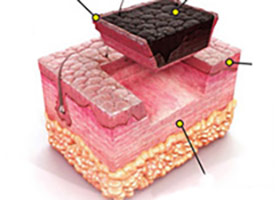

principle and development of water knife technology水刀技术通过独有组织细胞分离技术精准定位大汗腺,由发丝孔径大小的喷嘴喷射超高音速可调控的高压水流,系统采用了文丘里效应,通过无菌生理盐水水流粉碎、回吸异常大汗腺,同步实现安全便捷,术后创口自然美观,30分钟左右快速祛臭。

大汗腺数量、范 围、深度广泛的 重度腋臭、多汗 多毛的复合型腋臭等

大汗腺分布范围 较广、深度较大 的中度腋臭、多 汗型腋臭等

大汗腺数量相对 较少、深度较浅 的轻微腋臭、青 春期腋臭、儿童 腋臭等